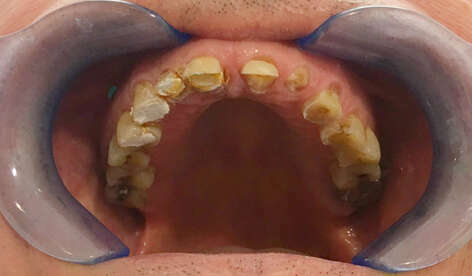

1. Restauration complète maxillaire et mandibulaire